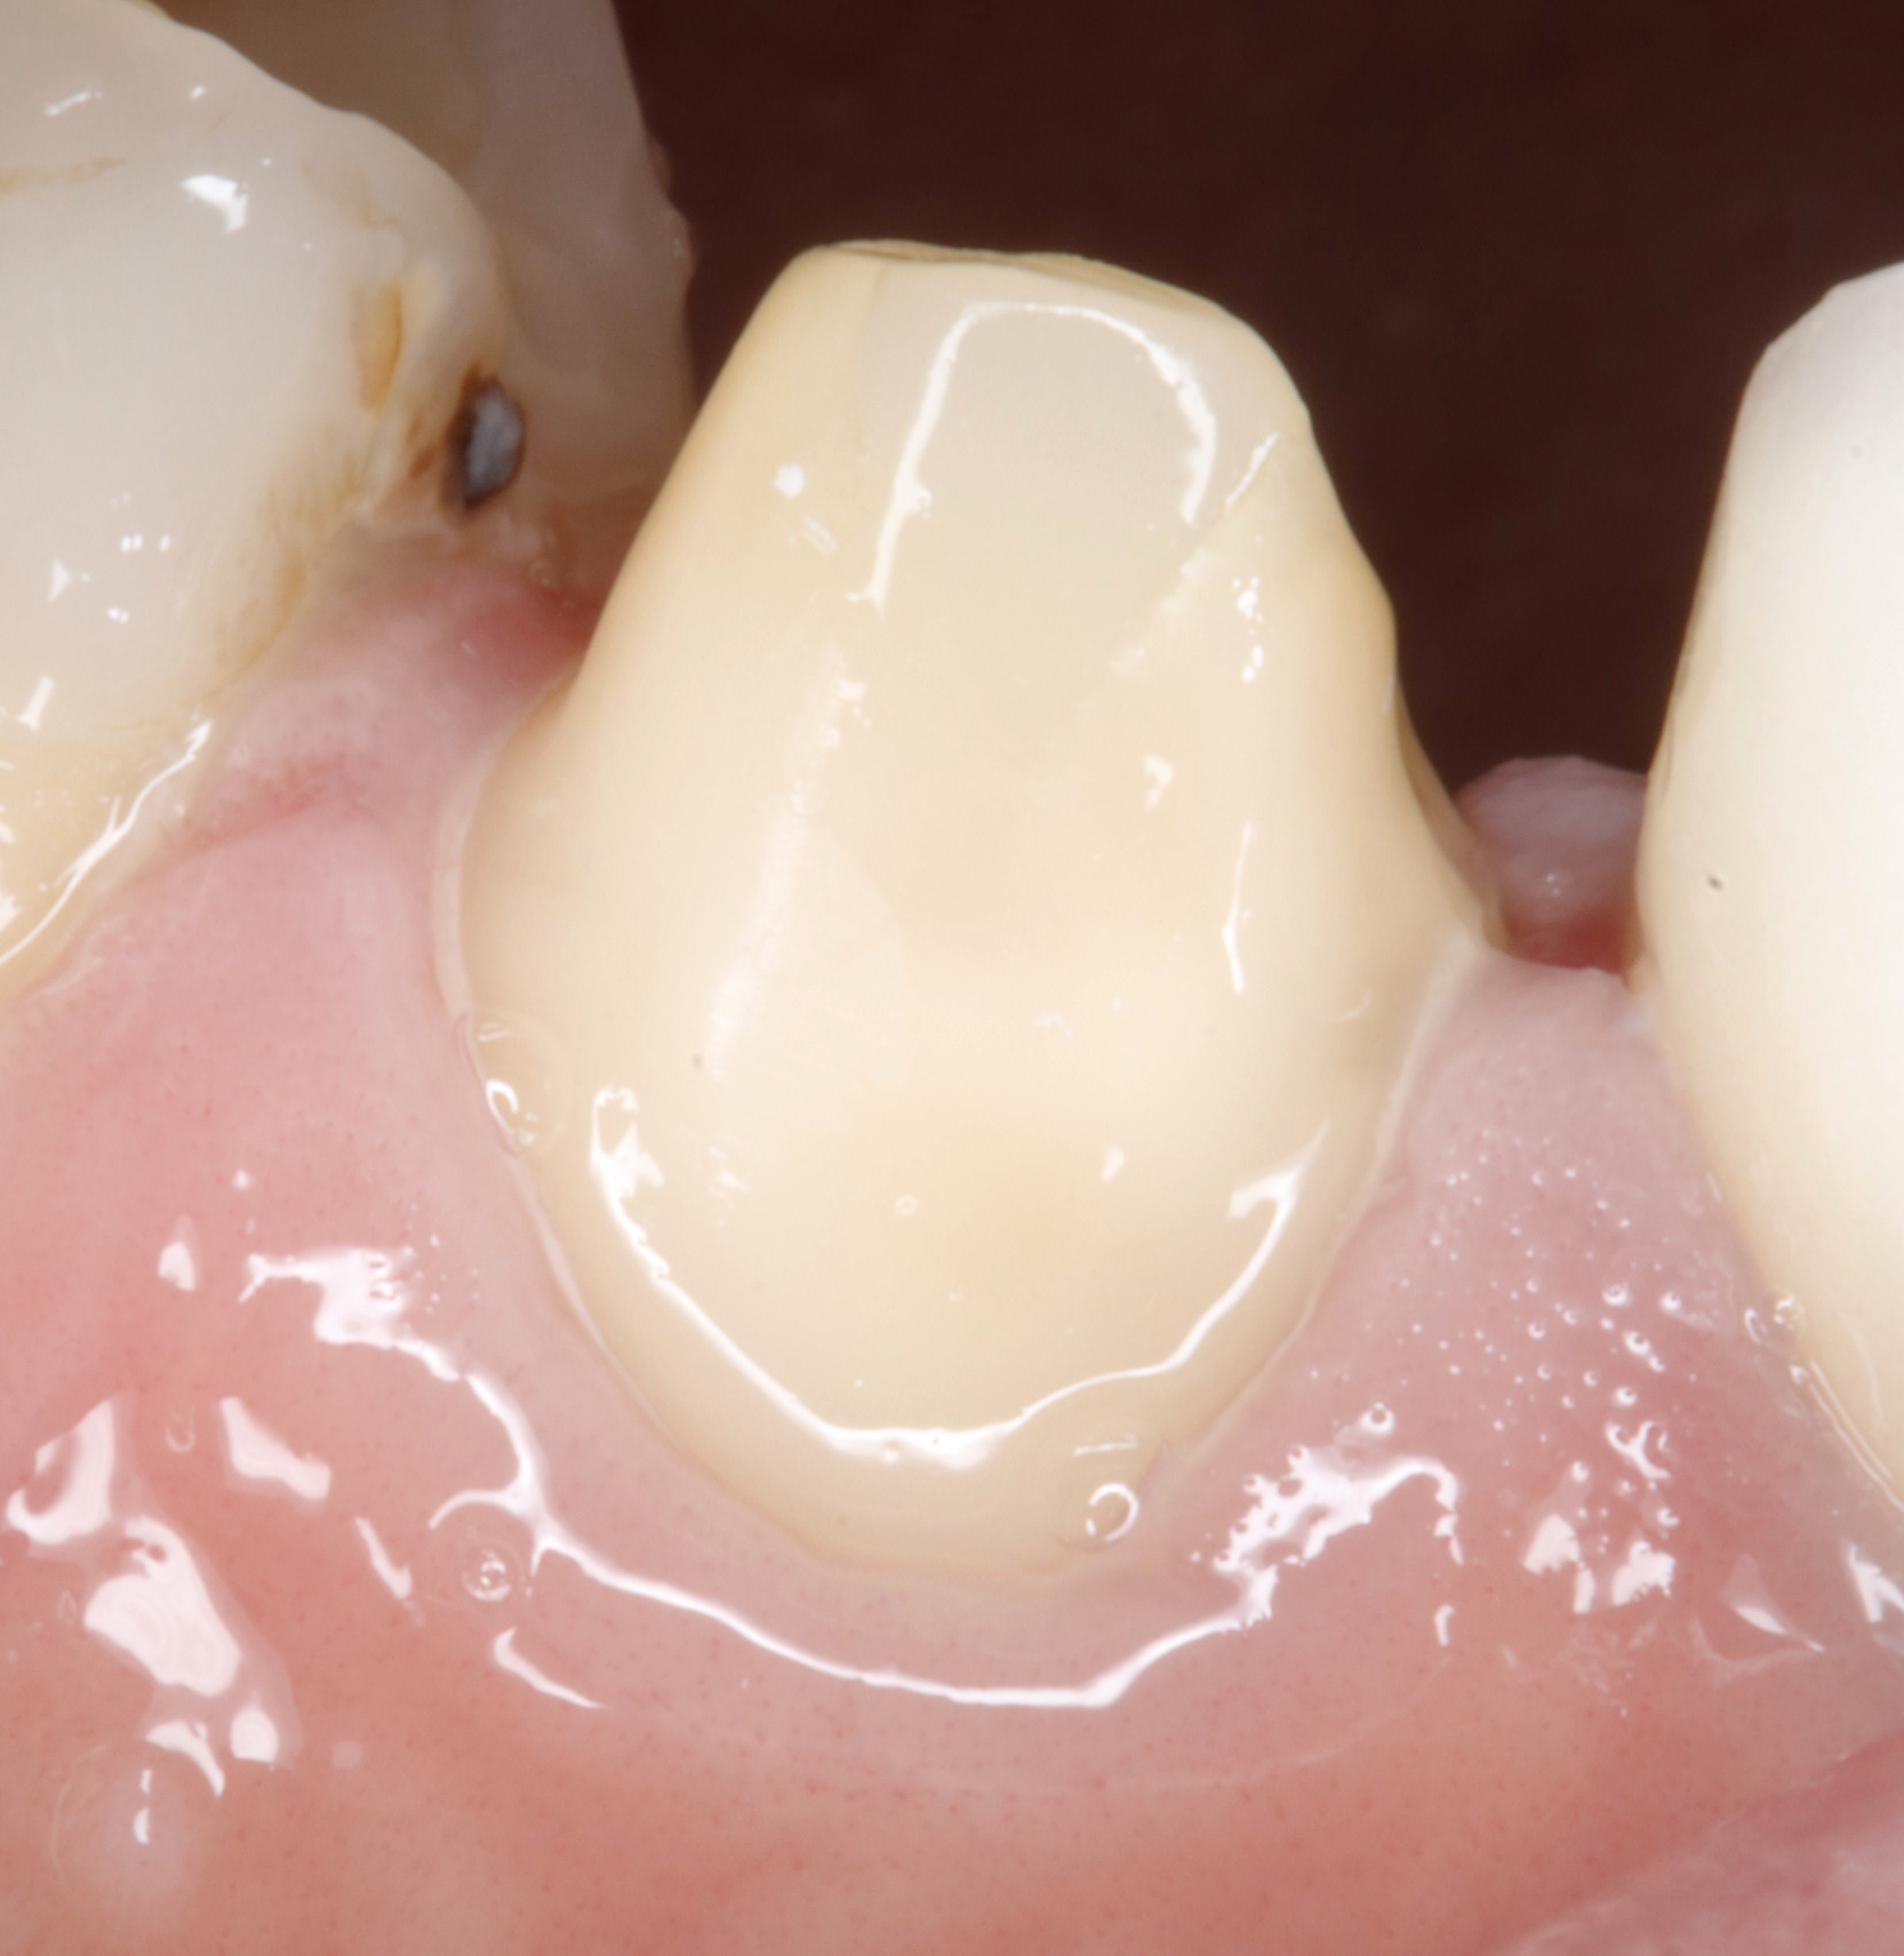

regarde c'est du gros moignon , Ca tiendra sans problème ... même en scellant si je veux

De de toute façon c'est une ancienne suceuse avec proalveolie . Même En propulsion elle ne les touche pas ses incisives

J'avais même pas besoin d'une empreinte antagoniste pour les faire puisqu'il y a pas de contact incisif

Lardonbis , tjs suite a ta question sur les limites mais en photo ,

voilà la taille de la page 25 , 1 semaine apres .

pourtant ,lors de la taille il n'y avait pas de fil , et la gencive pas trop touchée .

eh bien ,les limites apparaissent naturellement .